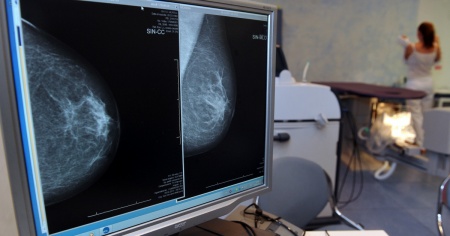

Uno studio apre a nuove cure per il tumore al seno

LONDRA - Le cellule del tumore della mammella sono capaci di mangiare e digerire la matrice extracellulare che le circonda pur di soddisfare la loro continua fame di energia. Lo dimostra lo studio coordinato dalla biotecnologa italiana Elena Rainero all'Università di Sheffield, nel Regno Unito. I risultati, pubblicati sulla rivista Plos Biology, fanno luce su un meccanismo di sopravvivenza delle cellule tumorali finora ignoto che potrebbe diventare il bersaglio di nuove terapie anti-cancro.